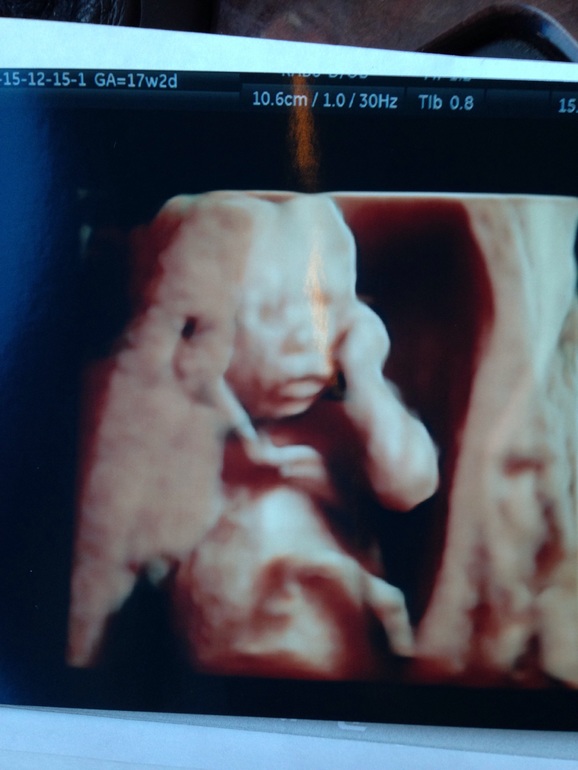

Узи нашей крошки)

Сказали девчонка, 207 гр)) моя губастенькая лапочка)) теперь привыкаю к мысли, что у нас будет доченька, я то всю жизнь была уверена, что у меня будет сын, уже и пару обновок "сынульке" прикупила 😄 Муж рад, что девочка, но нет-нет скажет "еще посмотрим, что 30 числа скажут". В этой связи вопрос, может ли девочка превратиться в мальчика?)) или я уже смело могу закупать платьица и бантики? Узи делали на сроке 17н 2 д.

Да, мне узист сказала, что лучшее время для 3d - 25-30 недель) и можно видео записать для семейного архива) я в этот раз делала обычное 2d узи, но на митунку включили 3d, сделали снимки, это было приятной неожиданностью)))